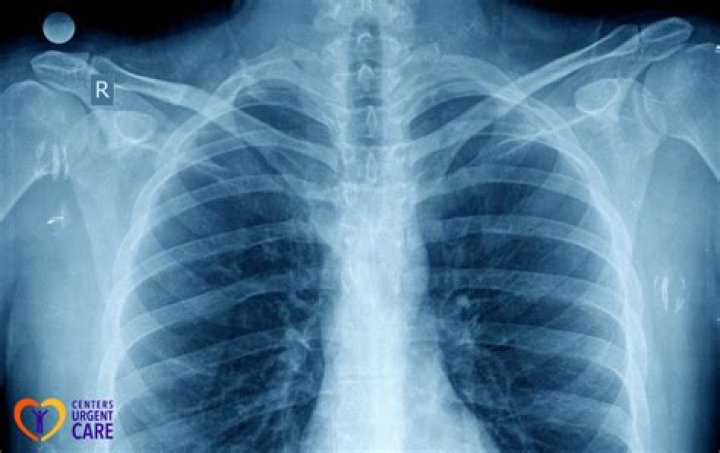

X-rays use beams of energy that pass through body tissues onto a special film and make a picture. They show pictures of your internal tissues, bones, and organs. Bone and metal show up as white on X-rays. X-rays of the belly may be done to check the area for causes of abdominal pain.